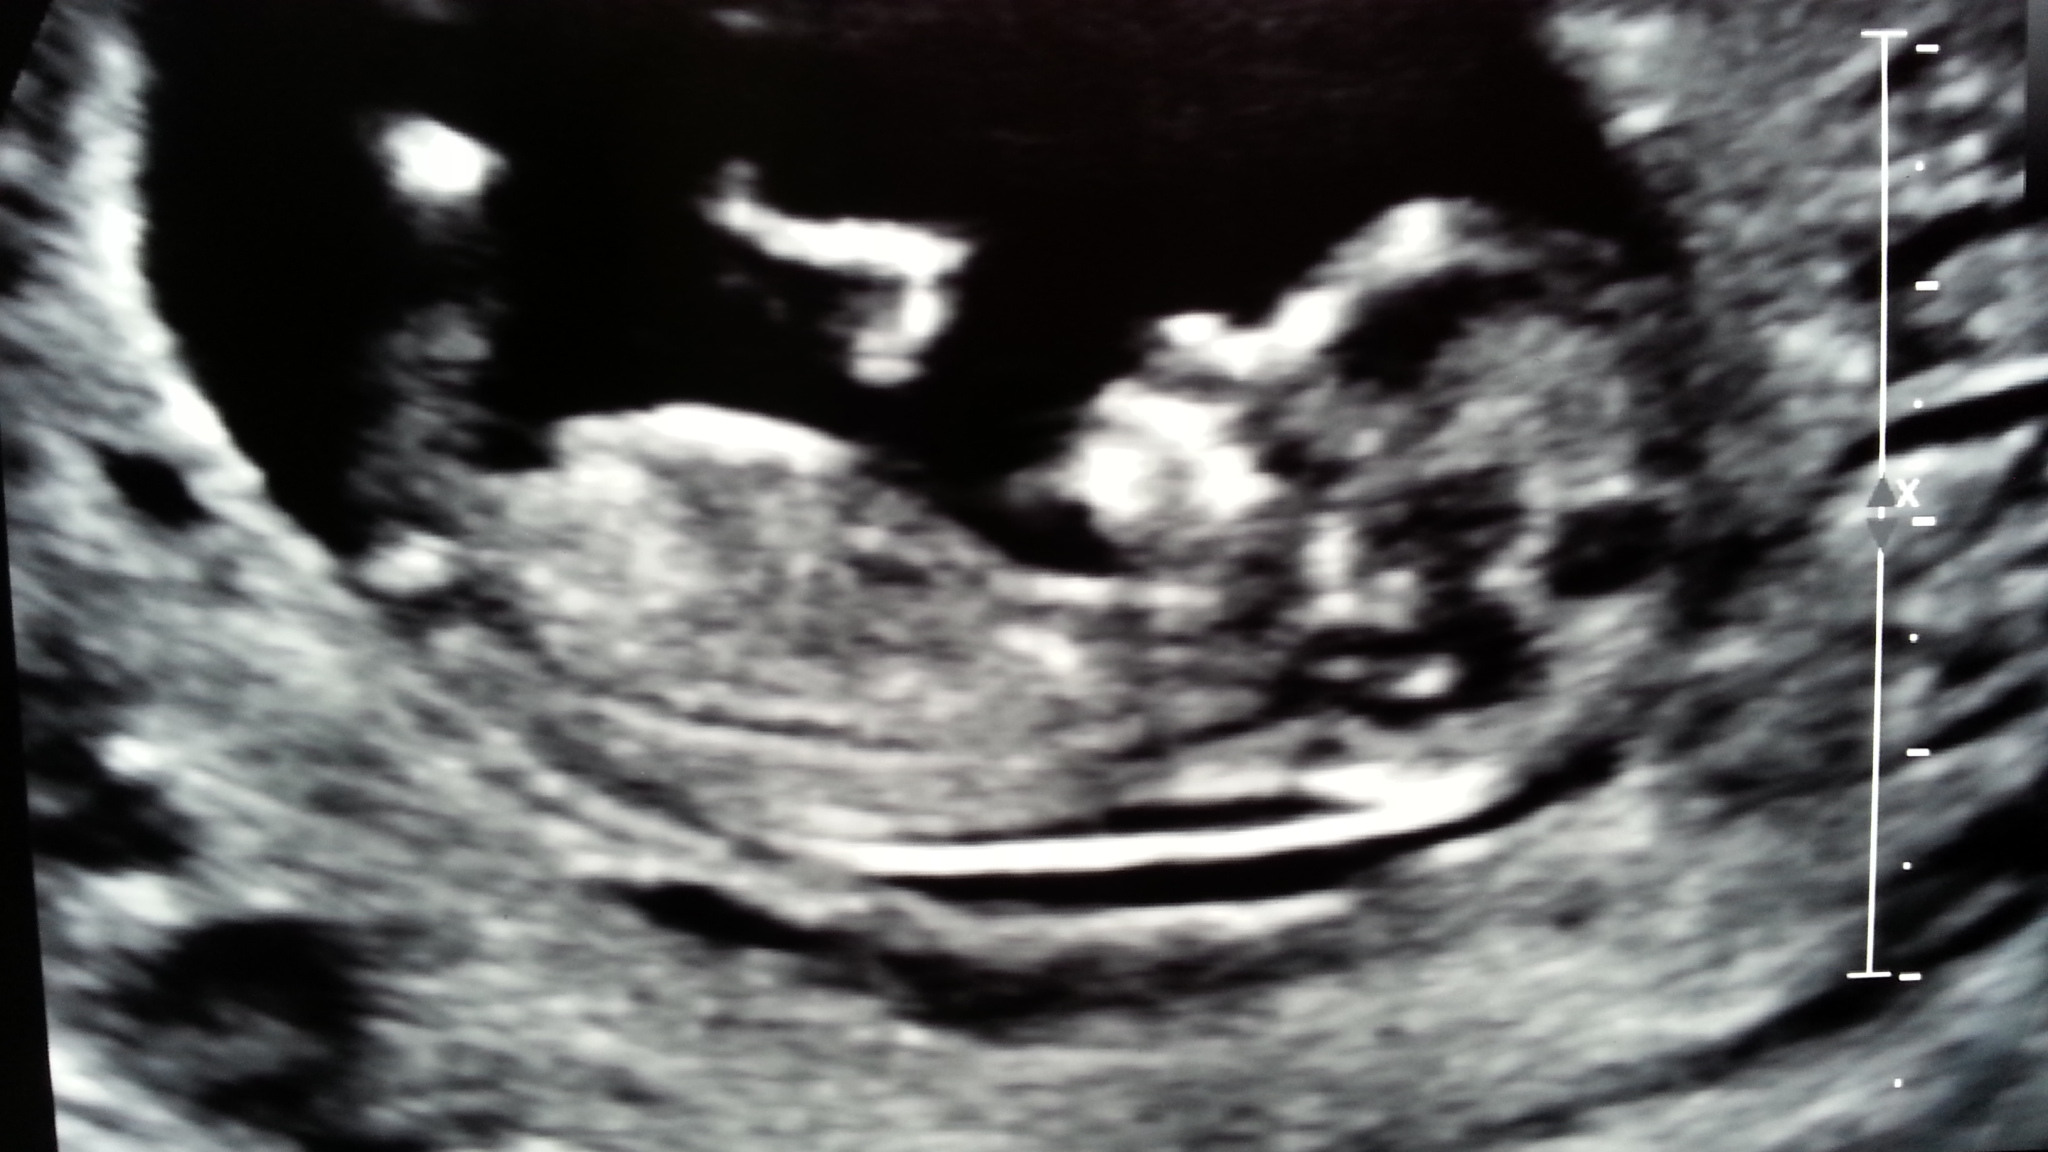

12+2wks baby being ridiculously uncooperative :-( not even sure I can make out a nub :-(

Any guesses greatly appreciated. Please be honest.

For some reason I'm really feeling boy.